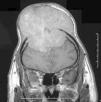

Leiomiosarcoma de cuero cabelludo.

Figuras (3)